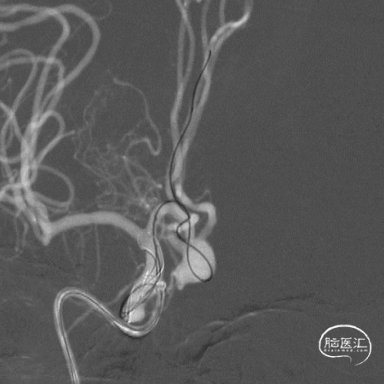

右侧Echelon-10瘤内成袢送入A2段,并解袢。

左侧Echelon-10瘤内成袢送入A2段,并解袢。

填入首枚10mm×30cm弹簧圈。

接续填入2枚9mm*30cm弹簧圈,再调整微管位置,送入4mm×12cm、4mm×10cm、3mm×8cm、2mm×6cm弹簧圈。